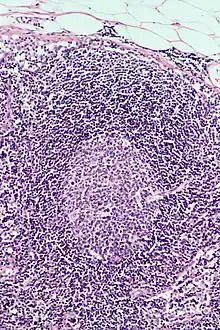

This is a list of Immune cells, also known as white blood cells, white cells, leukocytes, or leucocytes. They are cells involved in protecting the body against both infectious disease and foreign invaders.[1]

| Image | Name | Subtype | Class | Alternate Names | Diametere (μm) | Main targets | References |